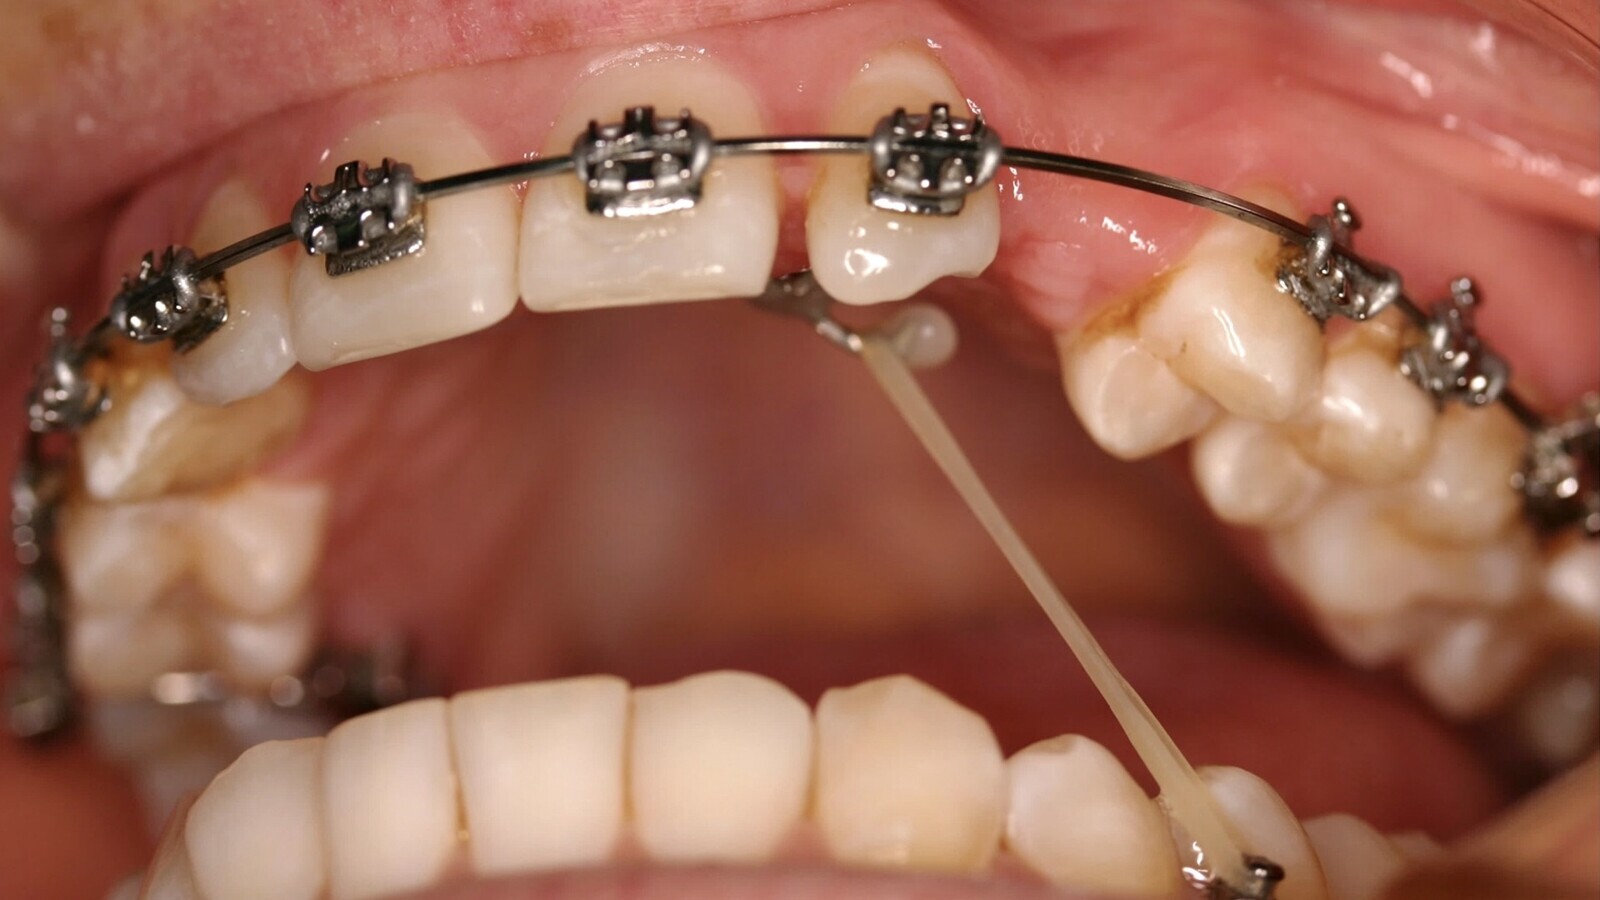

4. Utilizar siempre tracción vertical inicial (figura 13).

Figura 13. Los autores recomiendan utilizar siempre tracción vertical inicial.

6. Los Microimplantes son un excelente anclaje, seguro, indoloro, confortable y económico, para la tracción ortodóncica inicial de los caninos (figuras 14, 15 y 16).

Figuras 14, 15 y 16. Los Microimplantes son un excelente anclaje, seguro, indoloro, confortable y económico, para la tracción ortodóncica inicial de los caninos.

8. Una vez que se ha conseguido colocar en arcada la corona del canino, hay que realizar el trabajo hercúleo de dar torsión negativa a su raíz. Para ello recomendamos el uso de resortes en aleaciones de TMA o Gummetal con arcos gruesos (mínimo de 0.019x25”) y hacer entender al paciente la necesidad de tiempo para que el movimiento de torsión radicular negativa se produzca (figuras 17 y 18).

Figuras 17 y 18. Una vez colocada en arcada la corona del canino, hay que dar torsión negativa a su raíz. Se recomienda usar resortes en aleaciones de TMA o Gummetal con arcos gruesos.

9. En nuestra experiencia, las Microosteoperforaciones en el hueso enfrentado al movimiento dentario es una excelente opción para acelerar el movimiento dentario ortodóncico y acortar la duración del tratamiento. Estas Microosteoperforaciones, realizadas con una fresa de tugsteno a 2-4-7 mm de profundidad estimulan el RAP (rapid acelerated phenomen) y el reclutamiento de células progenitoras y osteoclastos (figuras 19 y 20).

Figuras 19 y 20. Las Microosteoperforaciones en el hueso enfrentado al movimiento dentario son una excelente opción para acelerar el movimiento dentario ortodóncico y acortar la duración del tratamiento.